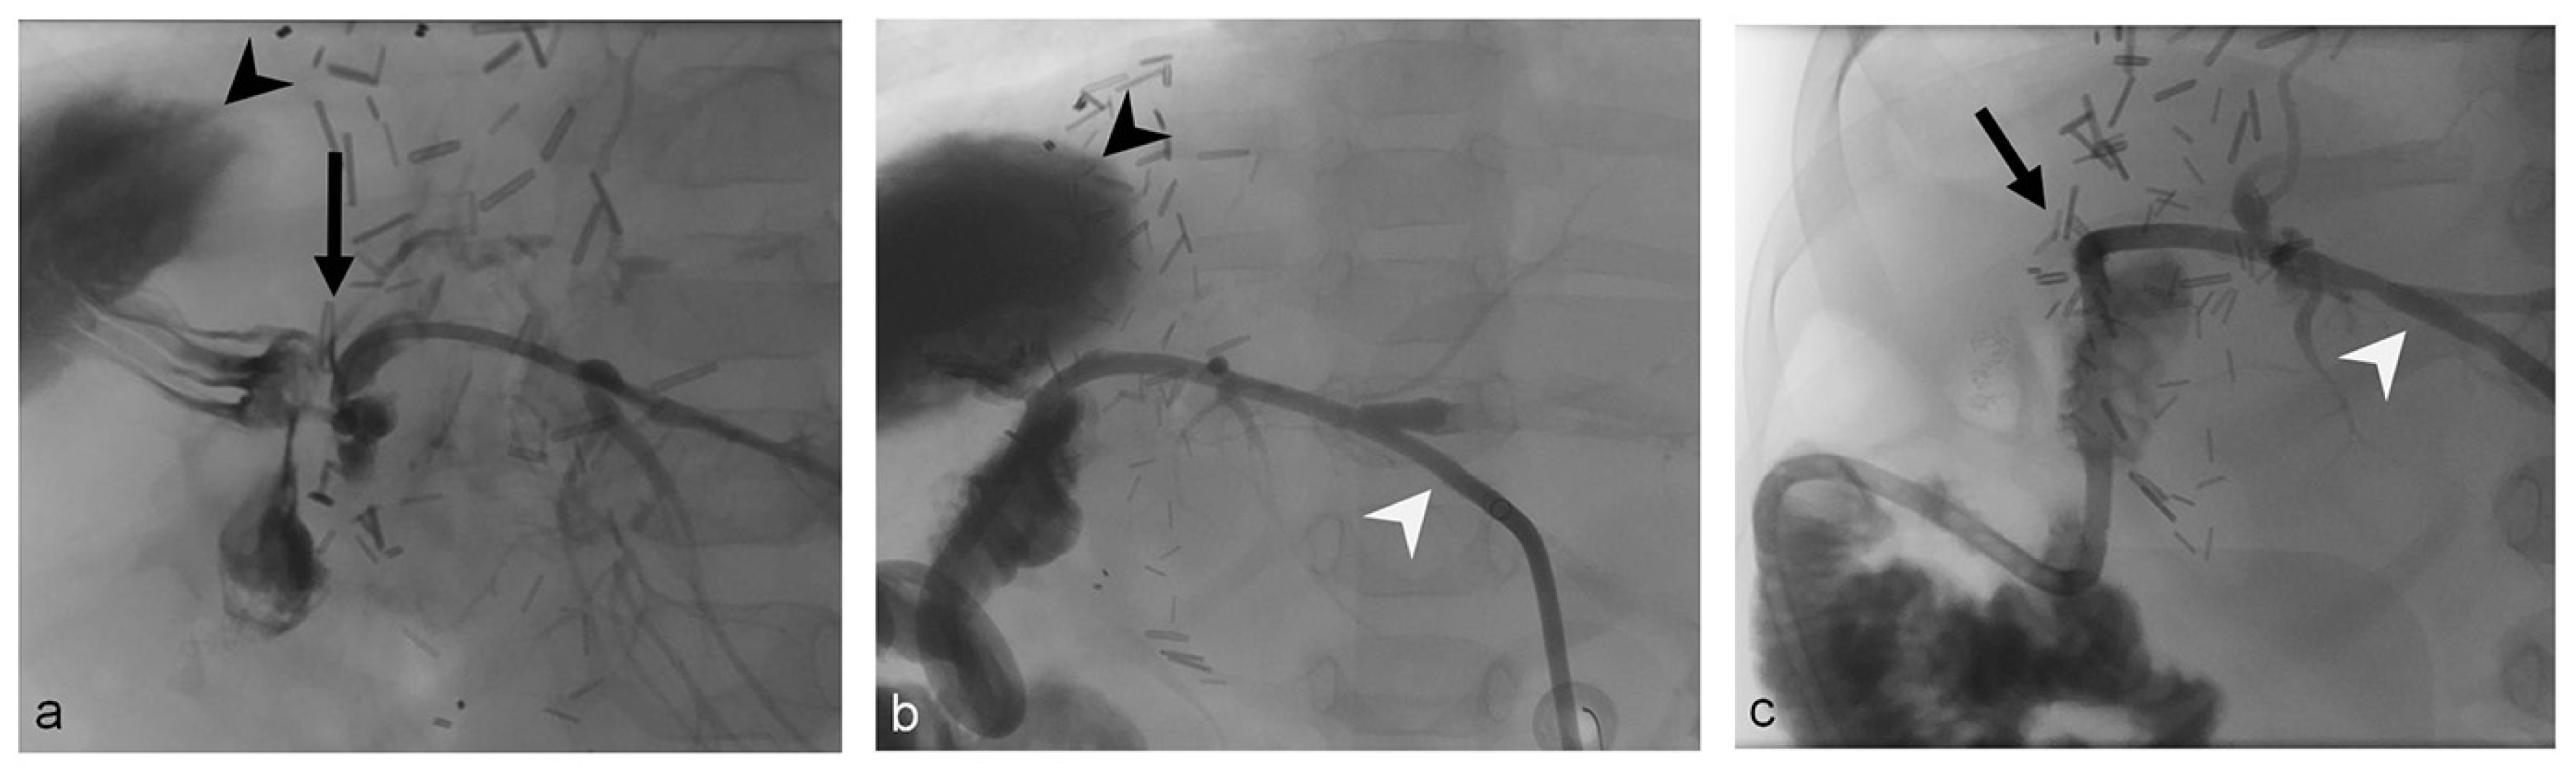

2.2. Procedure Technique

- Uller, W.; Wohlgemuth, W.A.; Hammer, S.; Knoppke, B.; Goessmann, H.; Loss, M.; Schlitt, H.J.; Stroszczynski, C.; Zorger, N.; Heiss, P. Percutaneous treatment of biliary complications in pediatric patients after liver transplantation. Rofo 2014, 186, 1127–1133. [Google Scholar] [CrossRef]